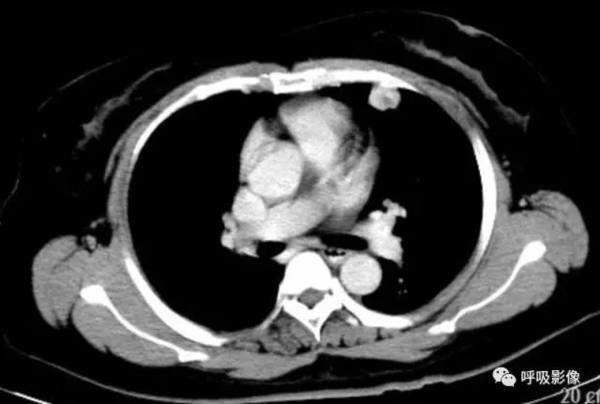

胸部CT示双肺多发结节影,强化明显,内见明显坏死,提示血供丰富。

转移瘤多具有原发肿瘤特点,本例转移瘤为生殖源性肿瘤,盆腔附件包块穿刺活检细胞学检病理均查见恶性肿瘤细胞,结合转移灶坏死、强化明显,需考虑绒毛膜癌缠医可能。

胸部CT双肺多发结节影,强化明显,内见明显坏死,提示血供丰富,这是诊断关键。